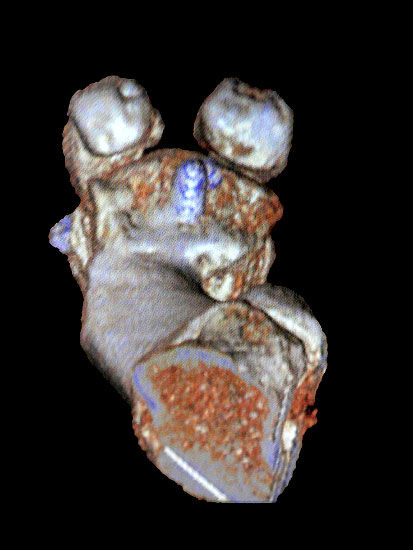

Avaskuläre Knochennekrose

Die Inzidenz der avaskulären Nekrose nach Osteotomie des Metatarsale I wird mit ca. 8% angegeben 1920. Neary et al. fanden in einer MRT Studie eine signifikante Reduktion der Durchblutung des Metatarsalekopfes und folgerten daraus ein erhebliches Risiko für eine Osteonekrose 21. Dem stehen die Resultate andere Studien entgegen die zwar eine Reduktion der Durchblutung beschreiben, allerdings trotzdem eine ausreichende Restdurchblutung fanden 2223. Neben der Osteotomie kann ein ausgedehntes laterales Release zu einer signifikanten Verschlechterung der Durchblutung führen.  Die von einigen Autoren postulierte Inzidenz von 8% kann von vielen Operateuren so nicht nachvollzogen werden19. Trotzdem gilt avaskuläre Nekrose als seltene, aber schwere Komplikation einer Hallux valgus Korrektur.

Kommt es zu einer avaskulären Nekrose, so  ist die Arthrodese kaum zu vermeiden (Abbildung 15). Ein biomechanisch relevanter Längenverlust kann durch die Interposition eines trikortikalen Beckenkammspans ausgeglichen werden (Abbildung 16). Defektzonen von bis zu einem Zentimeter lassen sich alternativ über eine distrahierende Scarf-Osteotomie ausgleichen, was mit einer geringeren Morbidität verbunden ist als eine Verlängerung mit Hilfe eines Knochentransplantats 24 (Abbildung 17). Bei der Präparation sollten die plantaren und lateralen Gefäße möglichst erhalten werden.